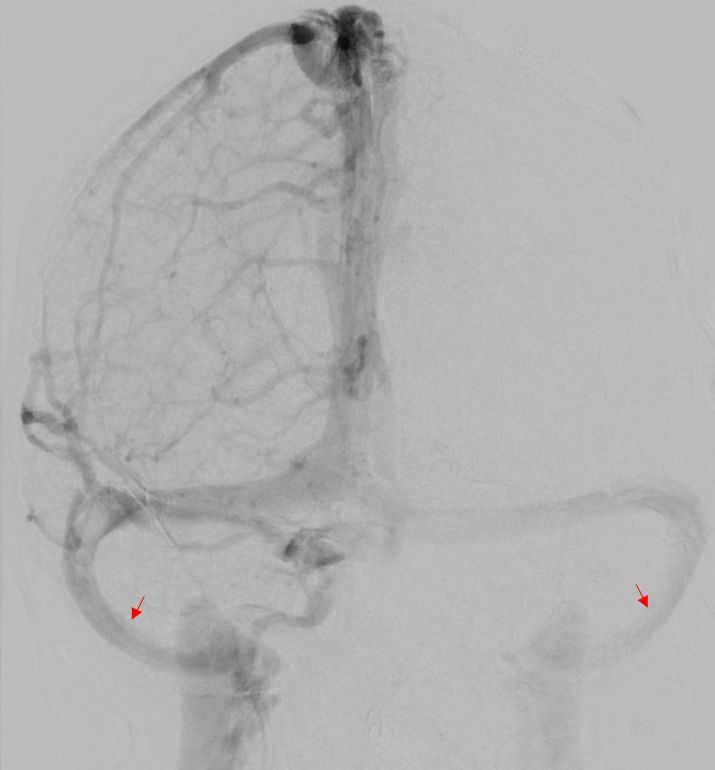

Sinus sigmoideus DSA

Darstellung des Sinus sigmoideus auf beiden Seiten in einer venösen Phase einer digitalen Subtraktionsangiographie.